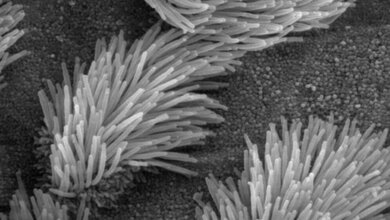

Jetzt hat das Team um Prof. Dr. Marcus Mall, damaliger und aktueller Studienleiter, erstmals untersucht, inwiefern diese Therapie auch langfristig, das heißt über mindestens zwölf Monate hinweg, hilft. Dafür haben die Forscherinnen und Forscher das Sputum, das Atemwegssekret, genauer betrachtet. „Bei Patientinnen/Patienten mit Mukoviszidose ist der Schleim in den Atemwegen sehr zäh, weil er zu wenig Wasser enthält und die schleimbildenden Moleküle, die sogenannten Muzine, zu stark chemisch miteinander verklebt sind. Der daraus resultierende zähe Schleim verstopft die Atemwege, erschwert damit die Atmung und führt bei den Betroffenen zu einer chronischen bakteriellen Infektion und Entzündung der Lunge“, erklärt Prof. Mall, Direktor der Klinik für Pädiatrie mit Schwerpunkt Pneumologie, Immunologie und Intensivmedizin und des Christiane Herzog Mukoviszidose-Zentrums der Charité.

Die Wissenschaftlerinnen und Wissenschaftler zeigen in der aktuellen Studie, dass die Dreifachtherapie mit Elexacaftor, Tezacaftor und Ivacaftor bei Patientinnen und Patienten mit Mukoviszidose dafür sorgt, dass das Atemwegssekret weniger zäh ist und die Entzündung und die bakterielle Infektion in der Lunge abnehmen. „Und das über die gesamte Dauer der Studie von einem Jahr. Das ist deshalb so bedeutsam, weil frühere Medikationen wieder zu einem Anstieg der Bakterienlast in den Atemwegen geführt hatten“, erläutert Dr. Simon Gräber, ebenfalls von der Klinik für Pädiatrie mit Schwerpunkt Pneumologie, Immunologie und Intensivmedizin der Charité und Co-Leiter der Studie. An dieser nahmen 79 Jugendliche und Erwachsene mit Mukoviszidose und einer chronischen Lungenerkrankung teil.

„Wir werden weiterhin intensiv daran forschen, wie Therapien, die Mukoviszidose über die krankheitsverursachenden molekularen Defekte angreifen – wie die jetzt untersuchte Dreifachmedikation – noch effektiver werden können. Hierzu gehört insbesondere ein früher Therapiebeginn im Kleinkindalter mit dem Ziel, chronische Lungenveränderungen möglichst zu verhindern“, berichtet Prof. Mall. „Außerdem steht diese Therapie für rund zehn Prozent unserer Patientinnen/Patienten aufgrund ihrer genetischen Voraussetzungen aktuell nicht zur Verfügung“, ergänzt Dr. Gräber. „Daher forschen wir auch mit Hochdruck an neuen molekularen Therapieansätzen, um alle Menschen mit Mukoviszidose effektiv behandeln zu können.“ Zudem arbeiten die Wissenschaftlerinnen und Wissenschaftler daran, die Fehlfunktion des Schleims bei Mukoviszidose besser zu verstehen und neue schleimlösende Wirkstoffe zu entwickeln. Davon sollen dann ebenfalls Patientinnen und Patienten mit häufigen chronisch-entzündlichen Lungenerkrankungen wie Asthma oder COPD profitieren.